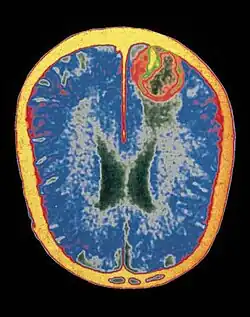

Neuroimagem

Diversos métodos de mapeamento cerebral são utilizados para compreender o cérebro humano.[40]